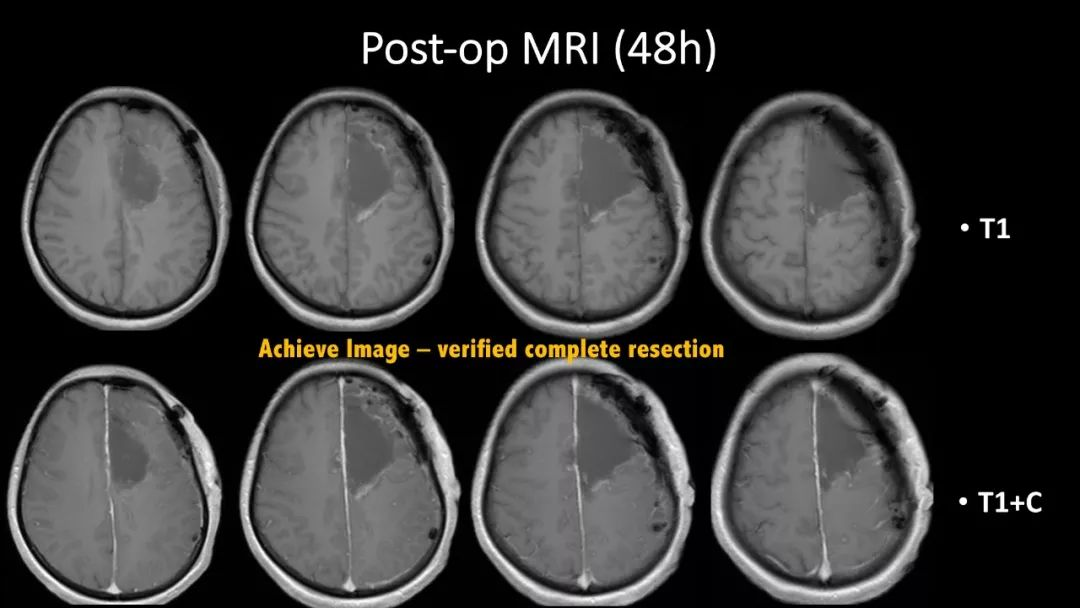

神外资讯将定期分享第一届“凝神聚胶”全国青年医师胶质瘤临床病例分析大赛的获奖病例。本期分享的病例是“二等奖”获得者——福建医科大学附属第一医院吴赞艺医师带来的:“Recurrent Anaplastic Oligodendroglioma Case Sharing(复发间变性少突胶质细胞瘤病例分享)”,欢迎观看、分享。